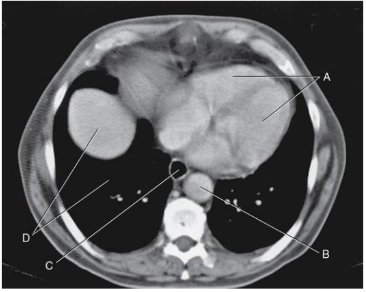

Tomografia do tórax é um exame que emprega radiação ionizante para obter cortes transversais dos tecidos localizados na área torácica. O teste revela detalhes de ossos, veias, artérias e pulmões, além de partes localizadas na porção entre os pulmões.

O corte tomográfico na imagem a seguir, próximo do nível de T10, demonstra a relação e o tamanho relativo a várias estruturas.

Nessa imagem, as estruturas identificadas são: